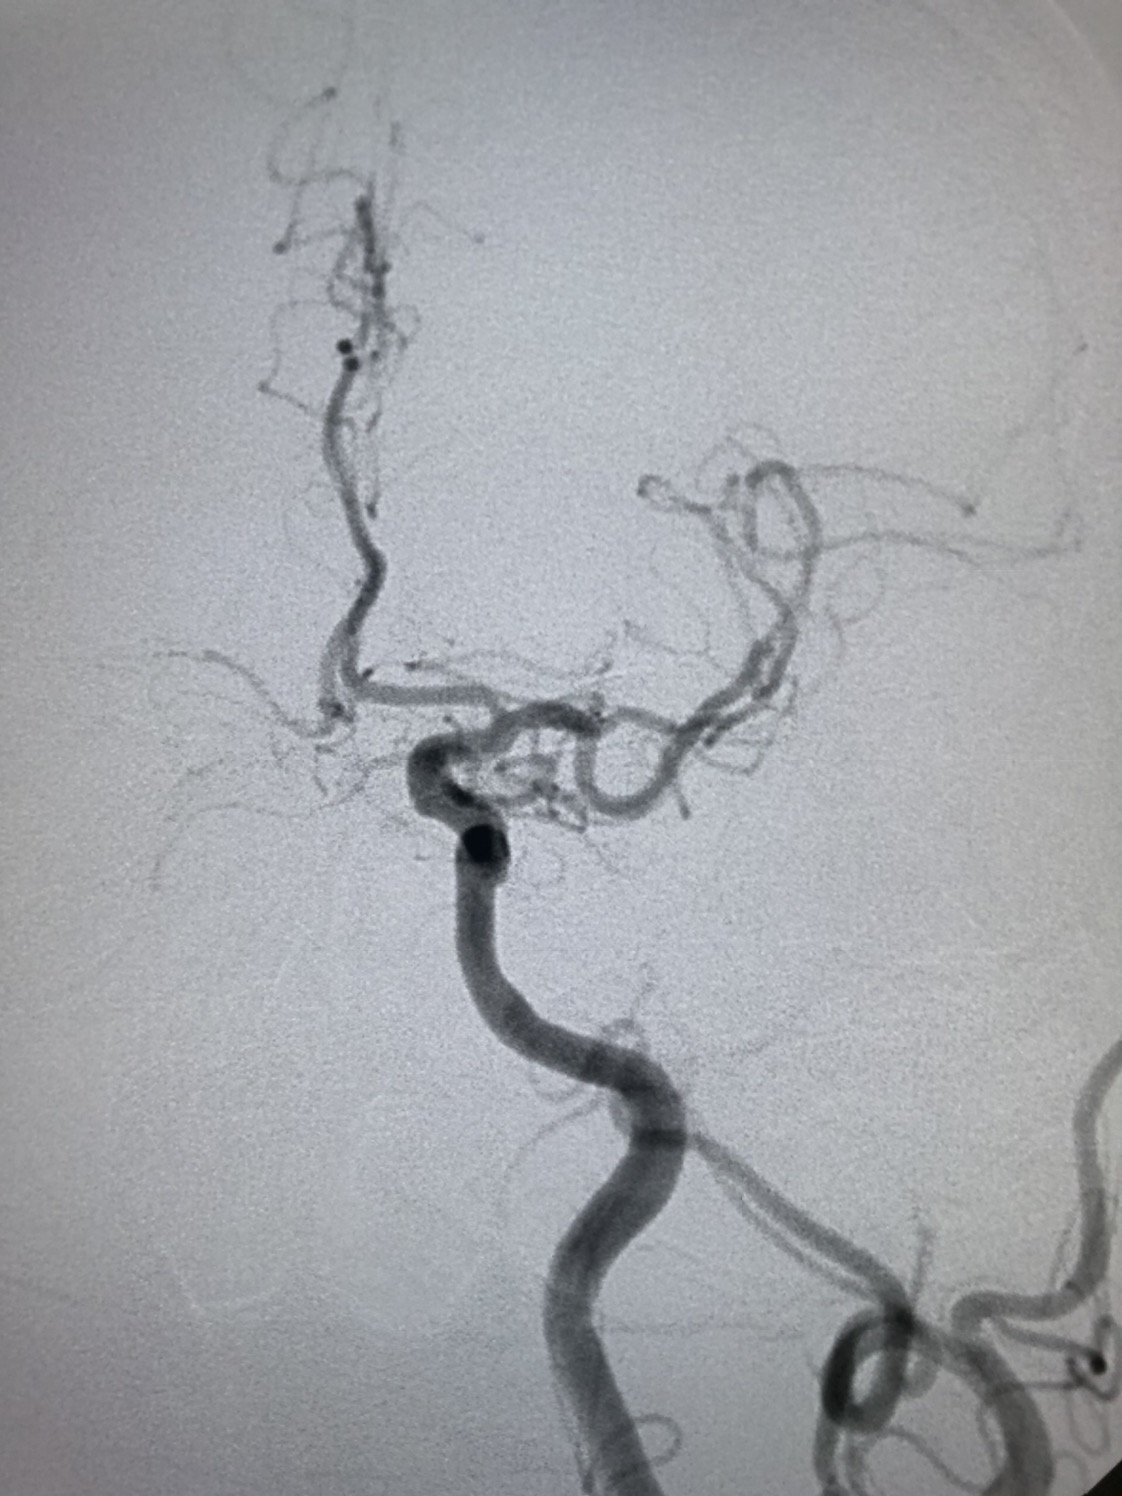

DSA:左侧颈内动脉起始部轻度狭窄。

DSA:左侧颈内动脉代偿右侧半球血供。